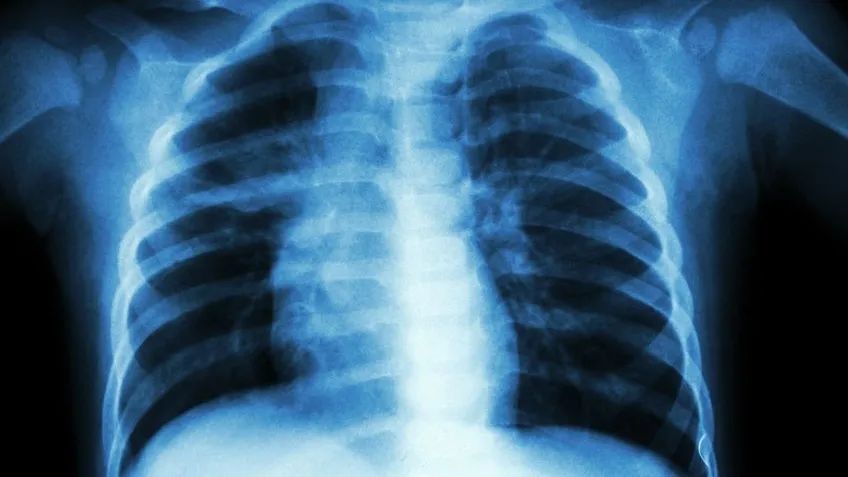

X光——像把面包压扁了看

常用于胸部、骨骼和四肢。

价格相对较便宜。原理是:X光会穿过人体,遇到被遮挡的部位,底片上不会曝光,洗片后这个部位就是白色的。

比如,大腿的骨头是圆的,可是片子上是平的,但可以看到其中丝丝缕缕的骨小梁。

X线检查可以拍头颅片、胸片、腹部平片、四肢的骨和关节片。一些胃部、食管和肠道疾病,也会用到X线检查,比如钡餐检查、消化道造影等。在日常体检时主要是用来拍胸片,筛查肺部的疾病。

乐乐摔了胳膊后,如果怀疑伤到了骨头,一般医生会优先选择拍个X光,检查结果快速易得。如果需要进一步观察,医生可能会选择CT观察细节,甚至磁共振成像观察隐匿损伤或软组织损伤。

有人说,拍片辐射大,甚至因诊断需要的拍片都拒拍,这种做法不可取。

X线检查的辐射剂量差不多是0.02—0.1mSv,和坐飞机飞行20小时接受的辐射差不多。每个人在日常生活中每年也会接受自然界辐射2.0—3.0mSv,所以X线检查是很安全的。

但是,孕妇做X线检查时需提前告知医生。